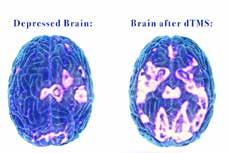

Deep TMS Therapy is a non-invasive treatment for depression, anxiety & OCD

3 - 4 times more effective than medication alone

Enhances Mood | Boost Neuroplasticity | Improves Focus

Provides lasting relief with minimal side effects

71% of patients had a 50% or greater reduction in depression symptoms at the Manhattan Clinic

Covered by all insurances (minus Medicaid)